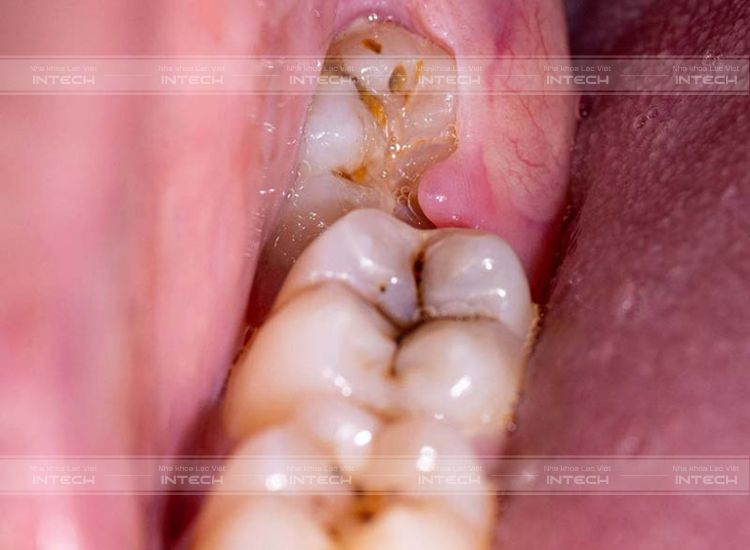

Áp xe được hình thành do răng khôn bị nhiễm trùngÁp xe được hình thành do răng khôn bị nhiễm trùng

Hình thành các túi mủHình thành các túi mủ

Áp xe tại chân răng

Tại chân răng hình thành các túi áp xe do bệnh lý sâu răng gây nên. Sau khi làm mòn men răng và ngà răng, vi khuẩn sẽ tấn công vào tủy răng khiến tủy răng bị viêm, mưng mủ và tạo ra các ổ mủ ở chân răng.